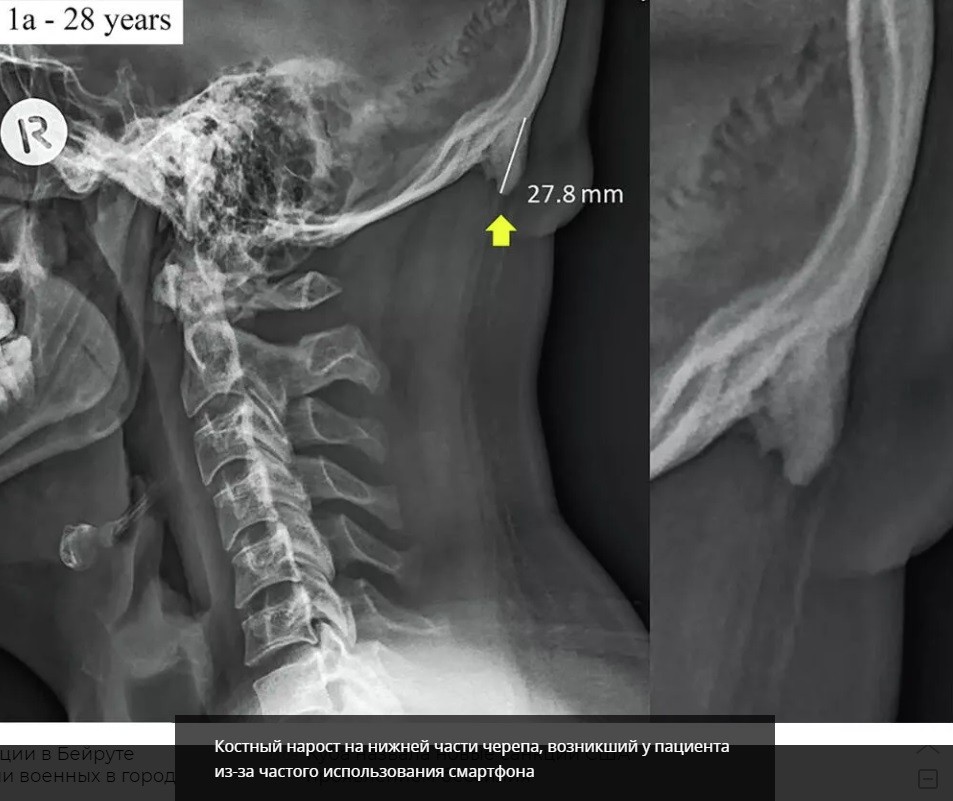

Согласно сразу нескольким работам австралийских ученых, смартфоны стимулируют рост определенных костей черепа. Речь идет о роговидных шипах — костных наростах на задней части черепа, образующихся из-за слишком частых наклонов головы.

Дело в том, что большинство людей, используя смартфон, непроизвольно наклоняют голову вперед — поближе к экрану. При этом вес тела переносится с позвоночника на мышцы задней части головы. В результате в сухожилиях и связках начинает расти кость — роговидный шип. В норме он не должен превышать трех миллиметров. Но почти у 41 процента добровольцев в возрасте до 30 лет (всего в рамках исследования осмотрели 1200 человек, из них 300 — в возрасте от 18 до 30 лет) его размер — от десяти до 31 миллиметра. Причем чаще эти "рога" встречались у мужчин.

Раньше такие костные наросты были характерны в основном для пожилых людей, большую часть жизни занимающихся тяжелой физической работой. Они, как правило, сопровождались хроническими головными болями, а также неприятными ощущениями в области шеи и позвоночника. Роговидные шипы, обнаруженные у молодых добровольцев, никакого дискомфорта им не доставляли. А в более старших возрастных группах эти костные наросты встречались гораздо реже.

Дополнительные исследования показали, что роговидные шипы — результат возросшей нагрузки на мышцы шейно-черепного отдела, а не генетическая болезнь или последствия перенесенных травм. Учитывая возраст обладателей рогов, единственный вариант, при котором им пришлось бы часто и подолгу держать голову слегка наклоненной вперед, — использование смартфонов, предполагают ученые.

Костный нарост на нижней части черепа, возникший у пациента из-за частого использования смартфона